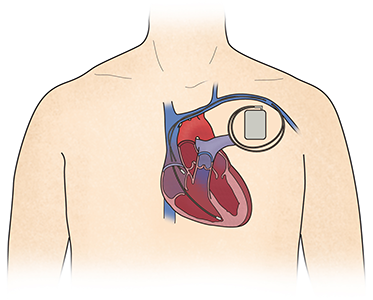

표준 약물치료에도 불구하고 심부전 증상이 있으면서 심장초음파상 박출률이 지속적으로 감소한 경우 기구치료(device therapy)를 검토하고 적응증에 해당되면 제세동기(ICD) 또는 심장재동기화치료(CRT)를 시행하고 이후에도 심부전 증상이 지속되거나 악화될 경우 2차 추가약물치료를 시행하게 됩니다. 이후에도 심부전 증상의 악화로 재입원을 반복하게 될 경우 중증 심부전에 대한 심기능을 상태를 평가하고 심장이식이나 LVAD를 고려할 수 있습니다.

- 삽입형 심실 제세동기 -